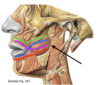

blue = palatoglossal folds

What forms the lateral wall of the oral vestibule?

cheek (buccae)

What is the cheek made up by?

- skin

- buccinator muscle

- buccopharyngeal fascia

- buccal glands

- buccal fat pad

- mucous membrane

What is the function of the buccinator muscle?

mastication/chewing

creates continuity between the oral cavity and the pharynx

What is the buccinator muscle attached to?

maxilla, mandible and pterygomandibular raphe, where it fuses with the pharyngeal constrictor

Where do the fibres of buccinator terminate and what muscle do they contribute to?

fibres terminate in both lips and contribute to orbicularis oris muscle

What is the point of cross over of the buccinator muscle fibres called?

modiolus

black = pyterygomandibular raphe